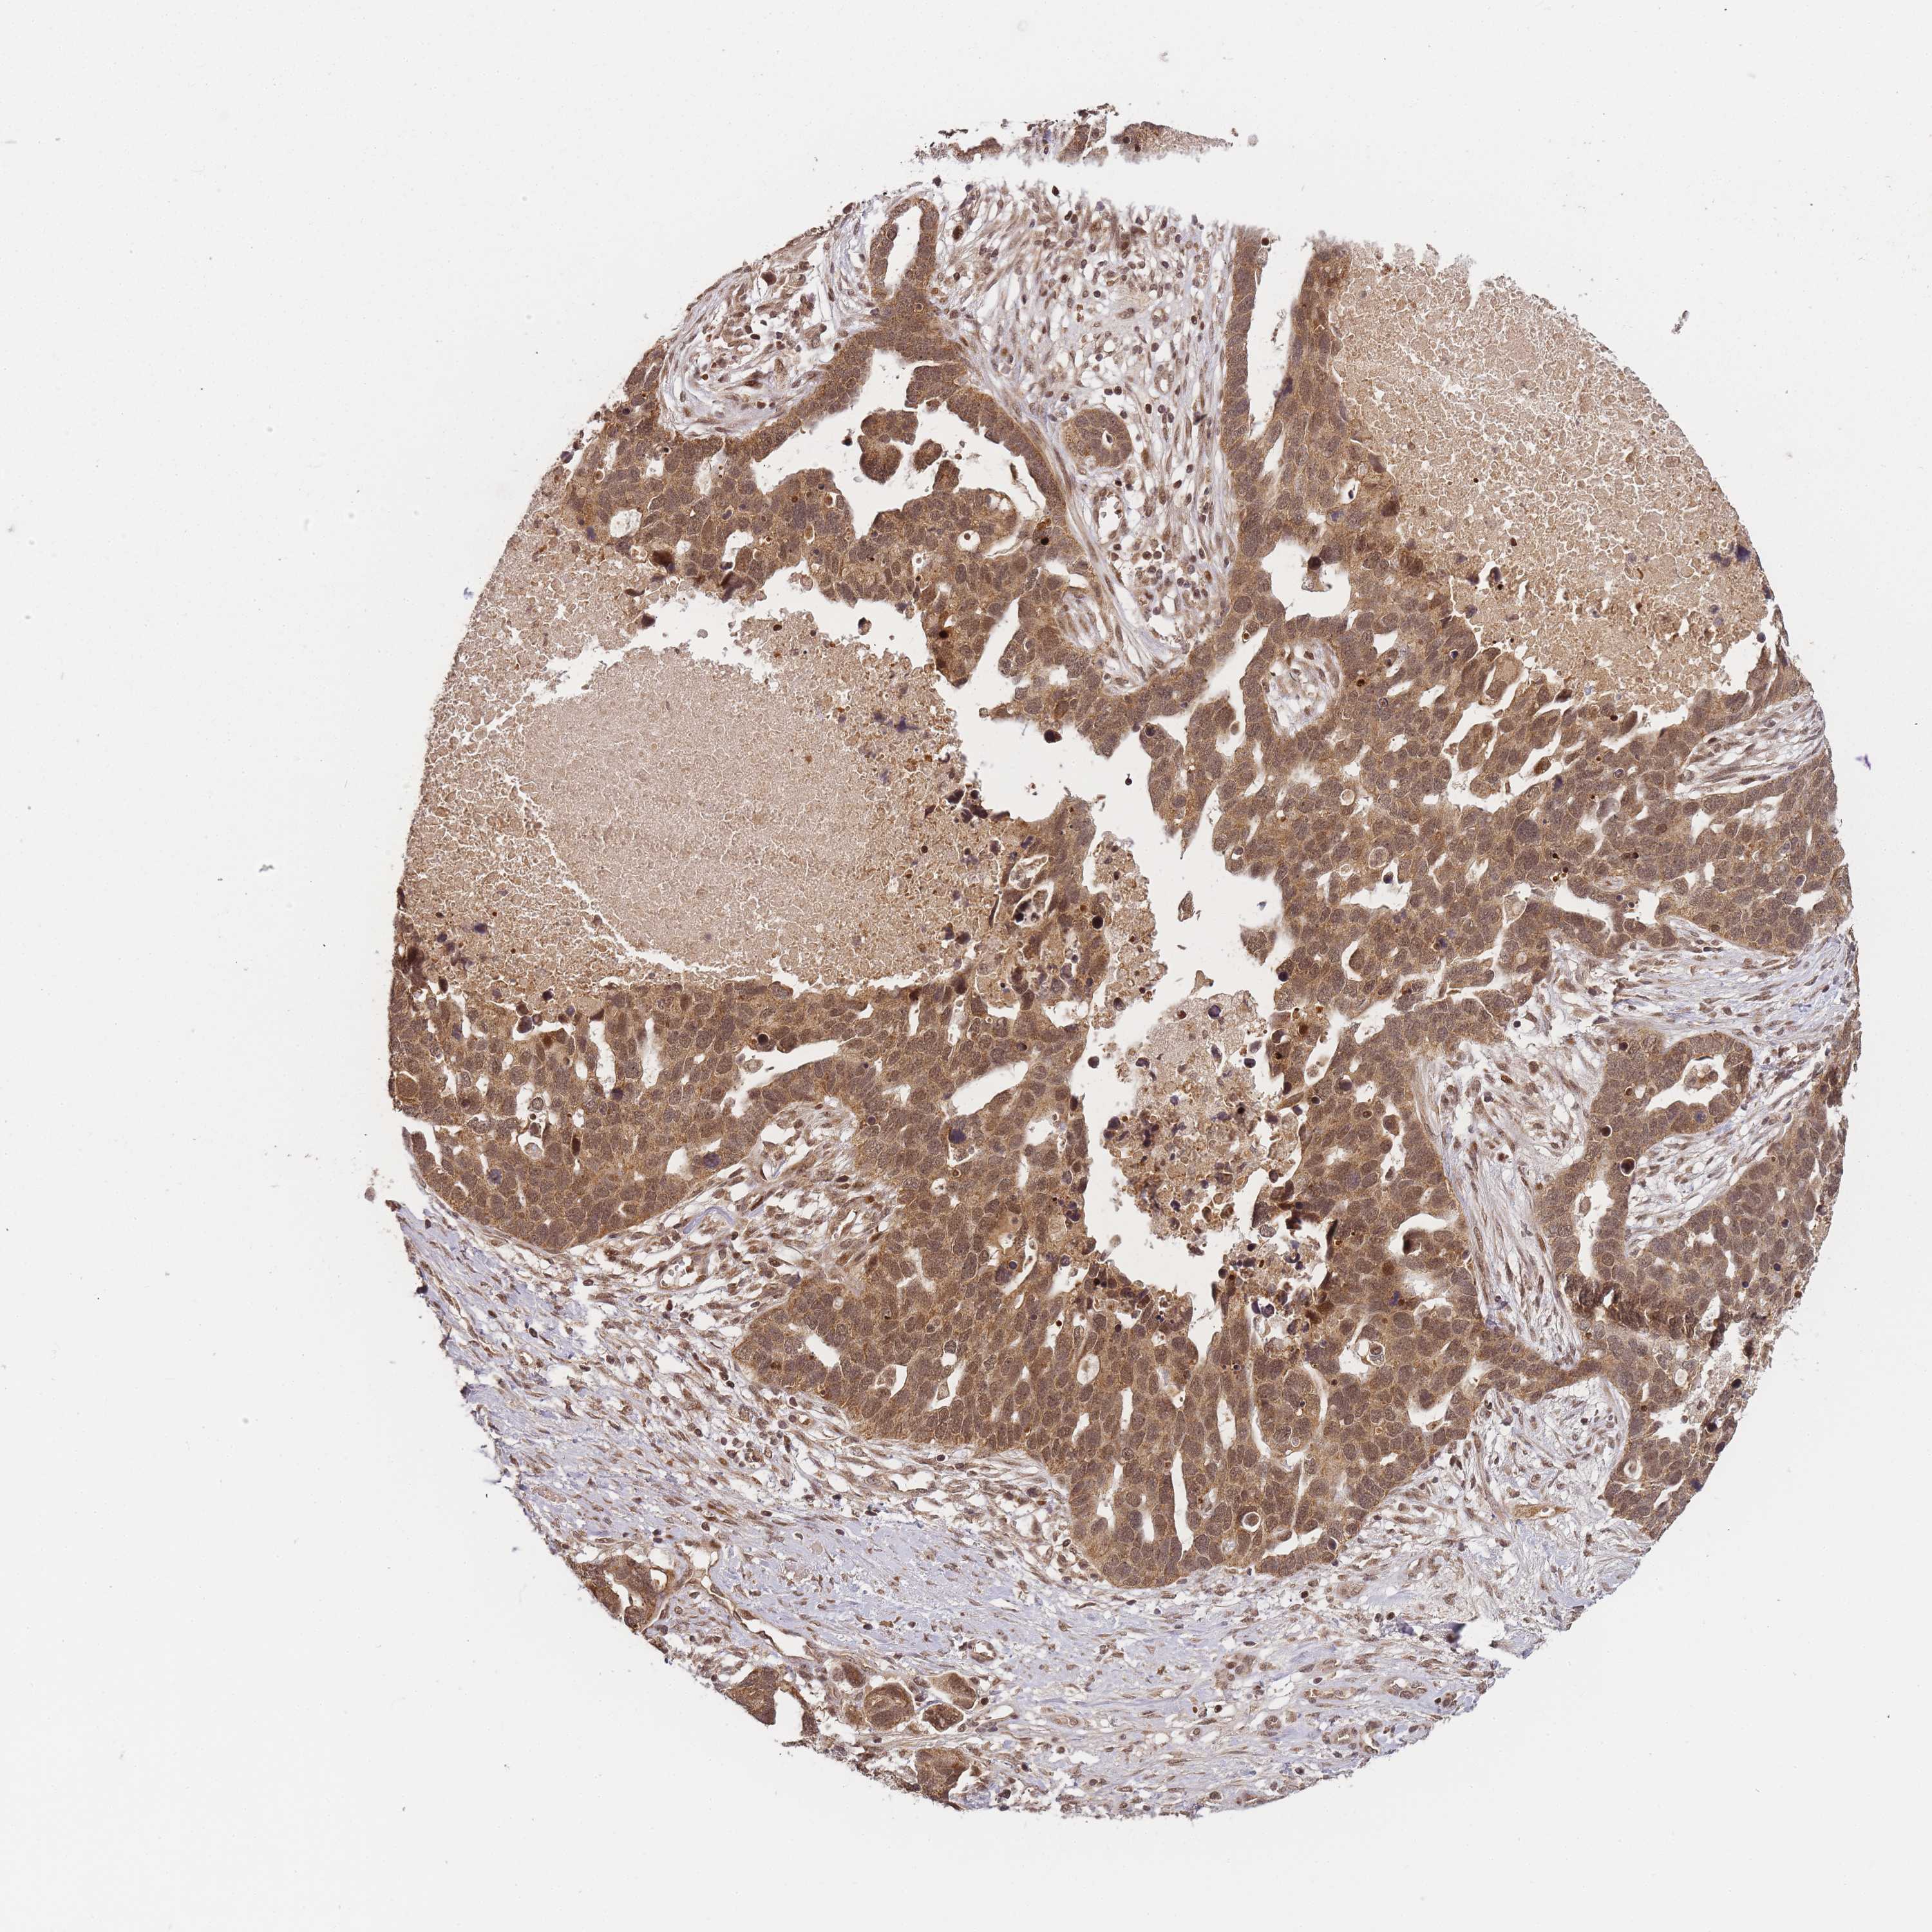

OVARIAN CANCER - Protein expressioni

A mouse-over function shows sample information and annotation data. Click on an image to view it in a full screen mode. Samples can be filtered based on level of antibody staining by selecting one or several of the following categories: high, medium, low and not detected. The assay and annotation is described here.

Note that samples used for immunohistochemistry by the Human Protein Atlas do not correspond to samples in the TCGA dataset.

Antibody stainingi

Antibody staining in the annotated cell types in the current human tissue is reported as not detected, low, medium, or high, based on conventional immunohistochemistry profiling in selected tissues. This score is based on the combination of the staining intensity and fraction of stained cells.

Each image is clickable and will lead to virtual microscopy that enables deeper exploration of all samples and also displays staining intensity scores, fraction scores and subcellular localization as well as patient and tissue information for each sample.

Antibody HPA047872

Staining

High

Medium

Low

Not detected

Intensity

Strong

Moderate

Weak

Negative

Quantity

>75%

75%-25%

<25%

None

Location

Nuclear

Cytoplasmic/membranous

Cytoplasmic/membranous,nuclear

Cystadenocarcinoma, serous, NOS

Carcinoma, NOS

Cystadenocarcinoma, mucinous, NOS

Carcinoma, endometroid